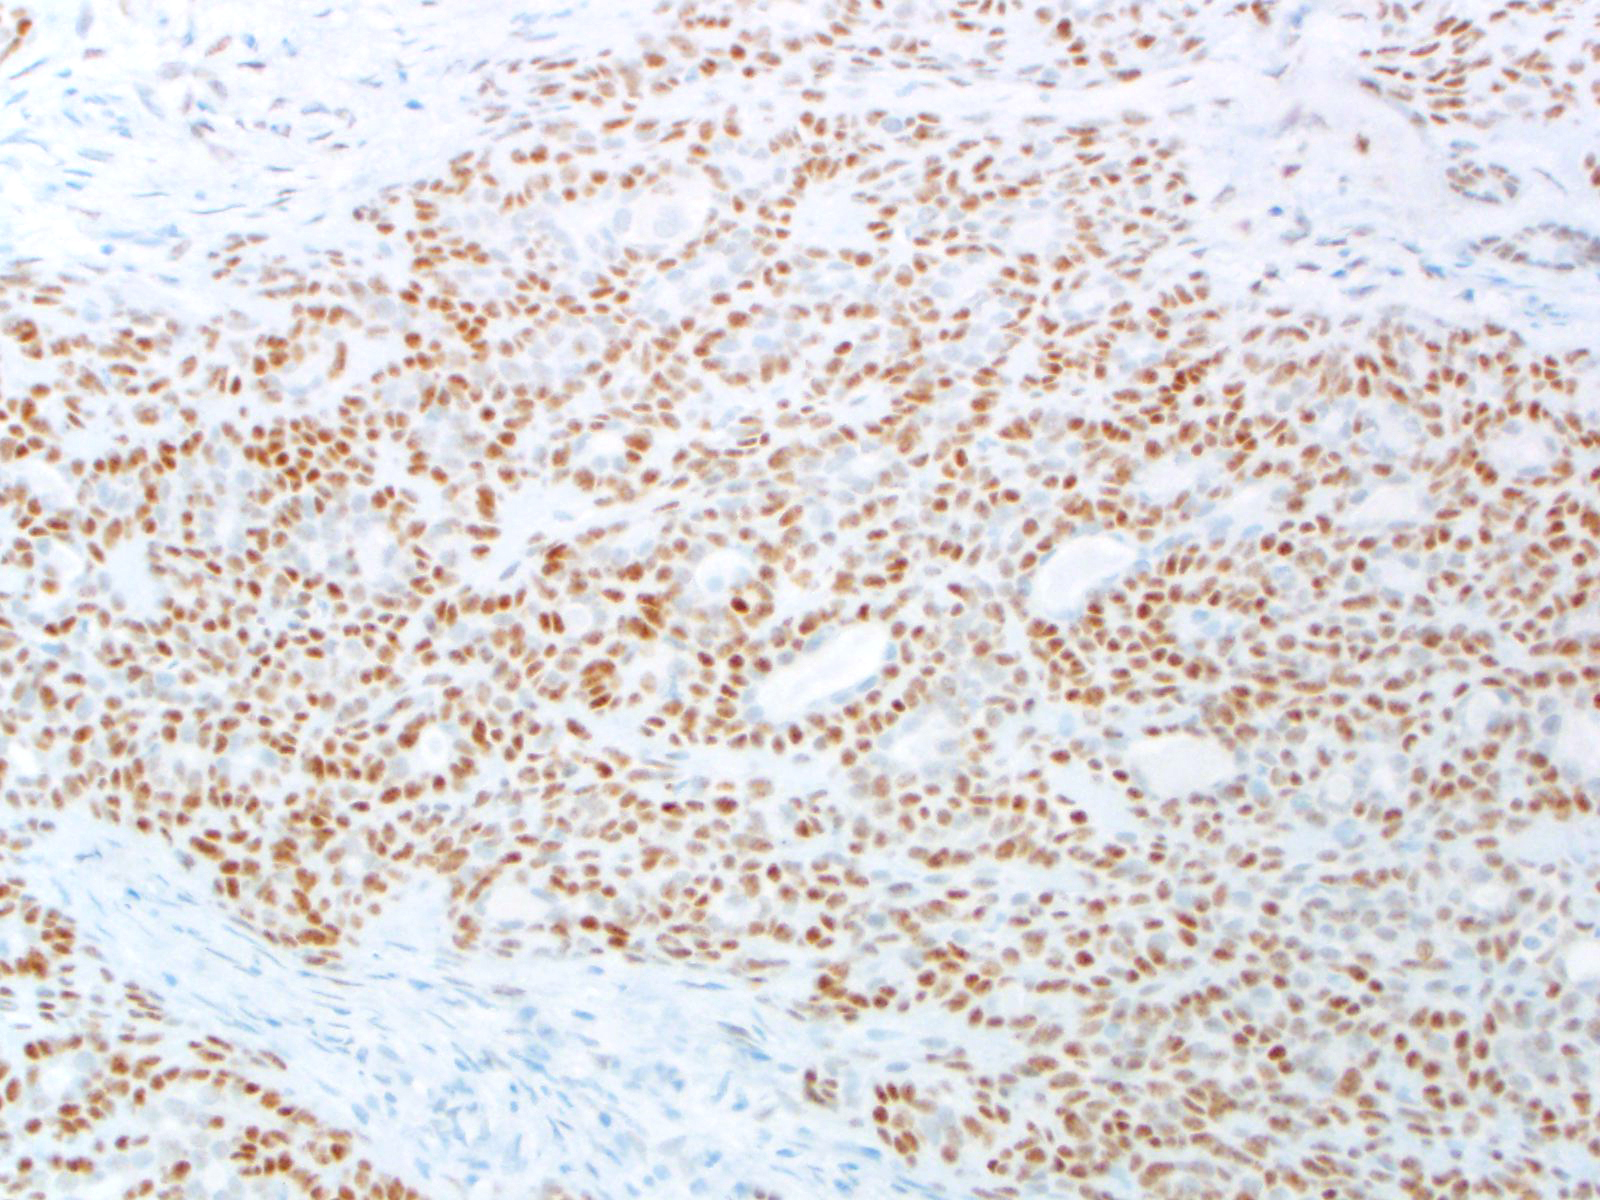

BCOR-associated tumors, including: BCOR-CCNB3 sarcoma, BCOR-MAML3 sarcoma, high-grade endometrial stromal sarcoma (ESS) harboring ZC3H7B-BCOR or BCOR internal tandem duplications (ITD), undifferentiated round cell sarcoma of young children harboring BCOR ITD, clear cell sarcoma of the kidney (CCSK) harboring BCOR ITD; EP300-BCOR pediatric glioma

Ewing sarcoma, CIC sarcoma, other sarcomas lacking BCOR alterations

Staining Pattern

Nuclear

| High-grade ESS |

| BCOR-CCNB3 sarcoma |

| Ewing sarcoma |